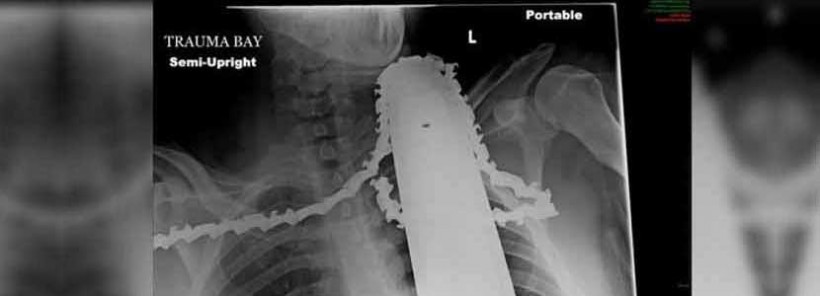

With over 36,000 chainsaw related injuries each year by thrifty home handymen, these simple techniques will save you money and maybe even an arm and a leg. ![]() Online PR News – 09-April-2019 – When you think of high-risk tasks and occupations, you probably think of serving in war-zones, bomb disposal experts, or commercial fishermen (86 fatal work injuries per 100,000 workers). The chances are that when you think of dicing with death for a living, or even just for fun, domestic tree trimming and removal isnt the top of your list. But did you know that there are over 36,000 chainsaw related injuries every year in the US alone? With figures like that, you really have to wonder why people bother to risk doing DIY instead of paying a professional, but unfortunately, this is what most people do. The average cost of hiring a tree trimmer was $438, whereas you could hire a chainsaw and give it a go yourself for just a fraction of the price at $67. Guided by a craving for savings rather than a desire not to lose a limb, swathes of people are taking matters into their own hands (or hand, depending on the type of accident they have.) Whilst yes, the prices of hiring a professional can be a little steep, especially for a family on a lower income, you have to ask what price people put on their health. Well the answer to that is, somewhere around $371. From 2009 – 2013 where total of 115,895 ED visits for injuries related to the use of a chainsaw occurred during the study period. Most injury visits occurred among males (95%) and persons aged 3059 years and during the months of September through November. The main body sites injured were the hand/fingers and knee. The majority of injuries were lacerations (80%). Is the risk to our health, and the subsequent bills, really worth it? Whilst you might save a few dollars initially, medical bills, time of work, and side effects of injury can cost you, much much more. Ben McInerney, a certified arborist from Go Tree Quotes, suggests how clients can saving money on tree services, without doing it yourself. There are plenty of ways to save tree services, and the biggest tip Im going to give you is hire in the colder months. As Ben explains, getting essential tree-trimming work done during the autumn or winter can save you at least 25% as arborists are a lot less busy at these times of year. Professionals working in the industry have a lot less work and are just trying to get by, so they are happy to take on projects at a lower cost in order to win your business. Its pure supply and demand, Ben continues, Companies are scratching around for work in winter so you are much more likely to get a better deal A big one is asking them to take the tree down and cut it up, and youll remove it there is a lot of manpower and expense in the actual removal of the tree. Get them to do the dangerous work, and you do the grunt work. He added; A real good money spinner is to actually sell any logs you have on eBay or Craigs list-not only do you save on the removal, but you make a profit on the waste material. The buyer will even come and take the logs away for you. Its a real win win Using Bens tips, not only can you save money on the cost of hiring a professional, but you can even make a bit of cash on the side, whilst retaining the function of all of your limbs and extremities. Not only this, but it is also better for the tree to be pruning it during the winter months. Ben explained; Youre always best off trimming trees while they are dormant in the colder months. As things start to switch back on in the spring they, the trees will find themselves with a lot less burden above ground in the form of branches and more reserves below the ground in the form of their vast root system to bloom back to life stronger and healthier than ever before. The moral of the story is, that whilst on the surface, you might think you are saving money by doing it yourself, the reality is that you could be risking your health, your bank balance, and even the health of your trees. |